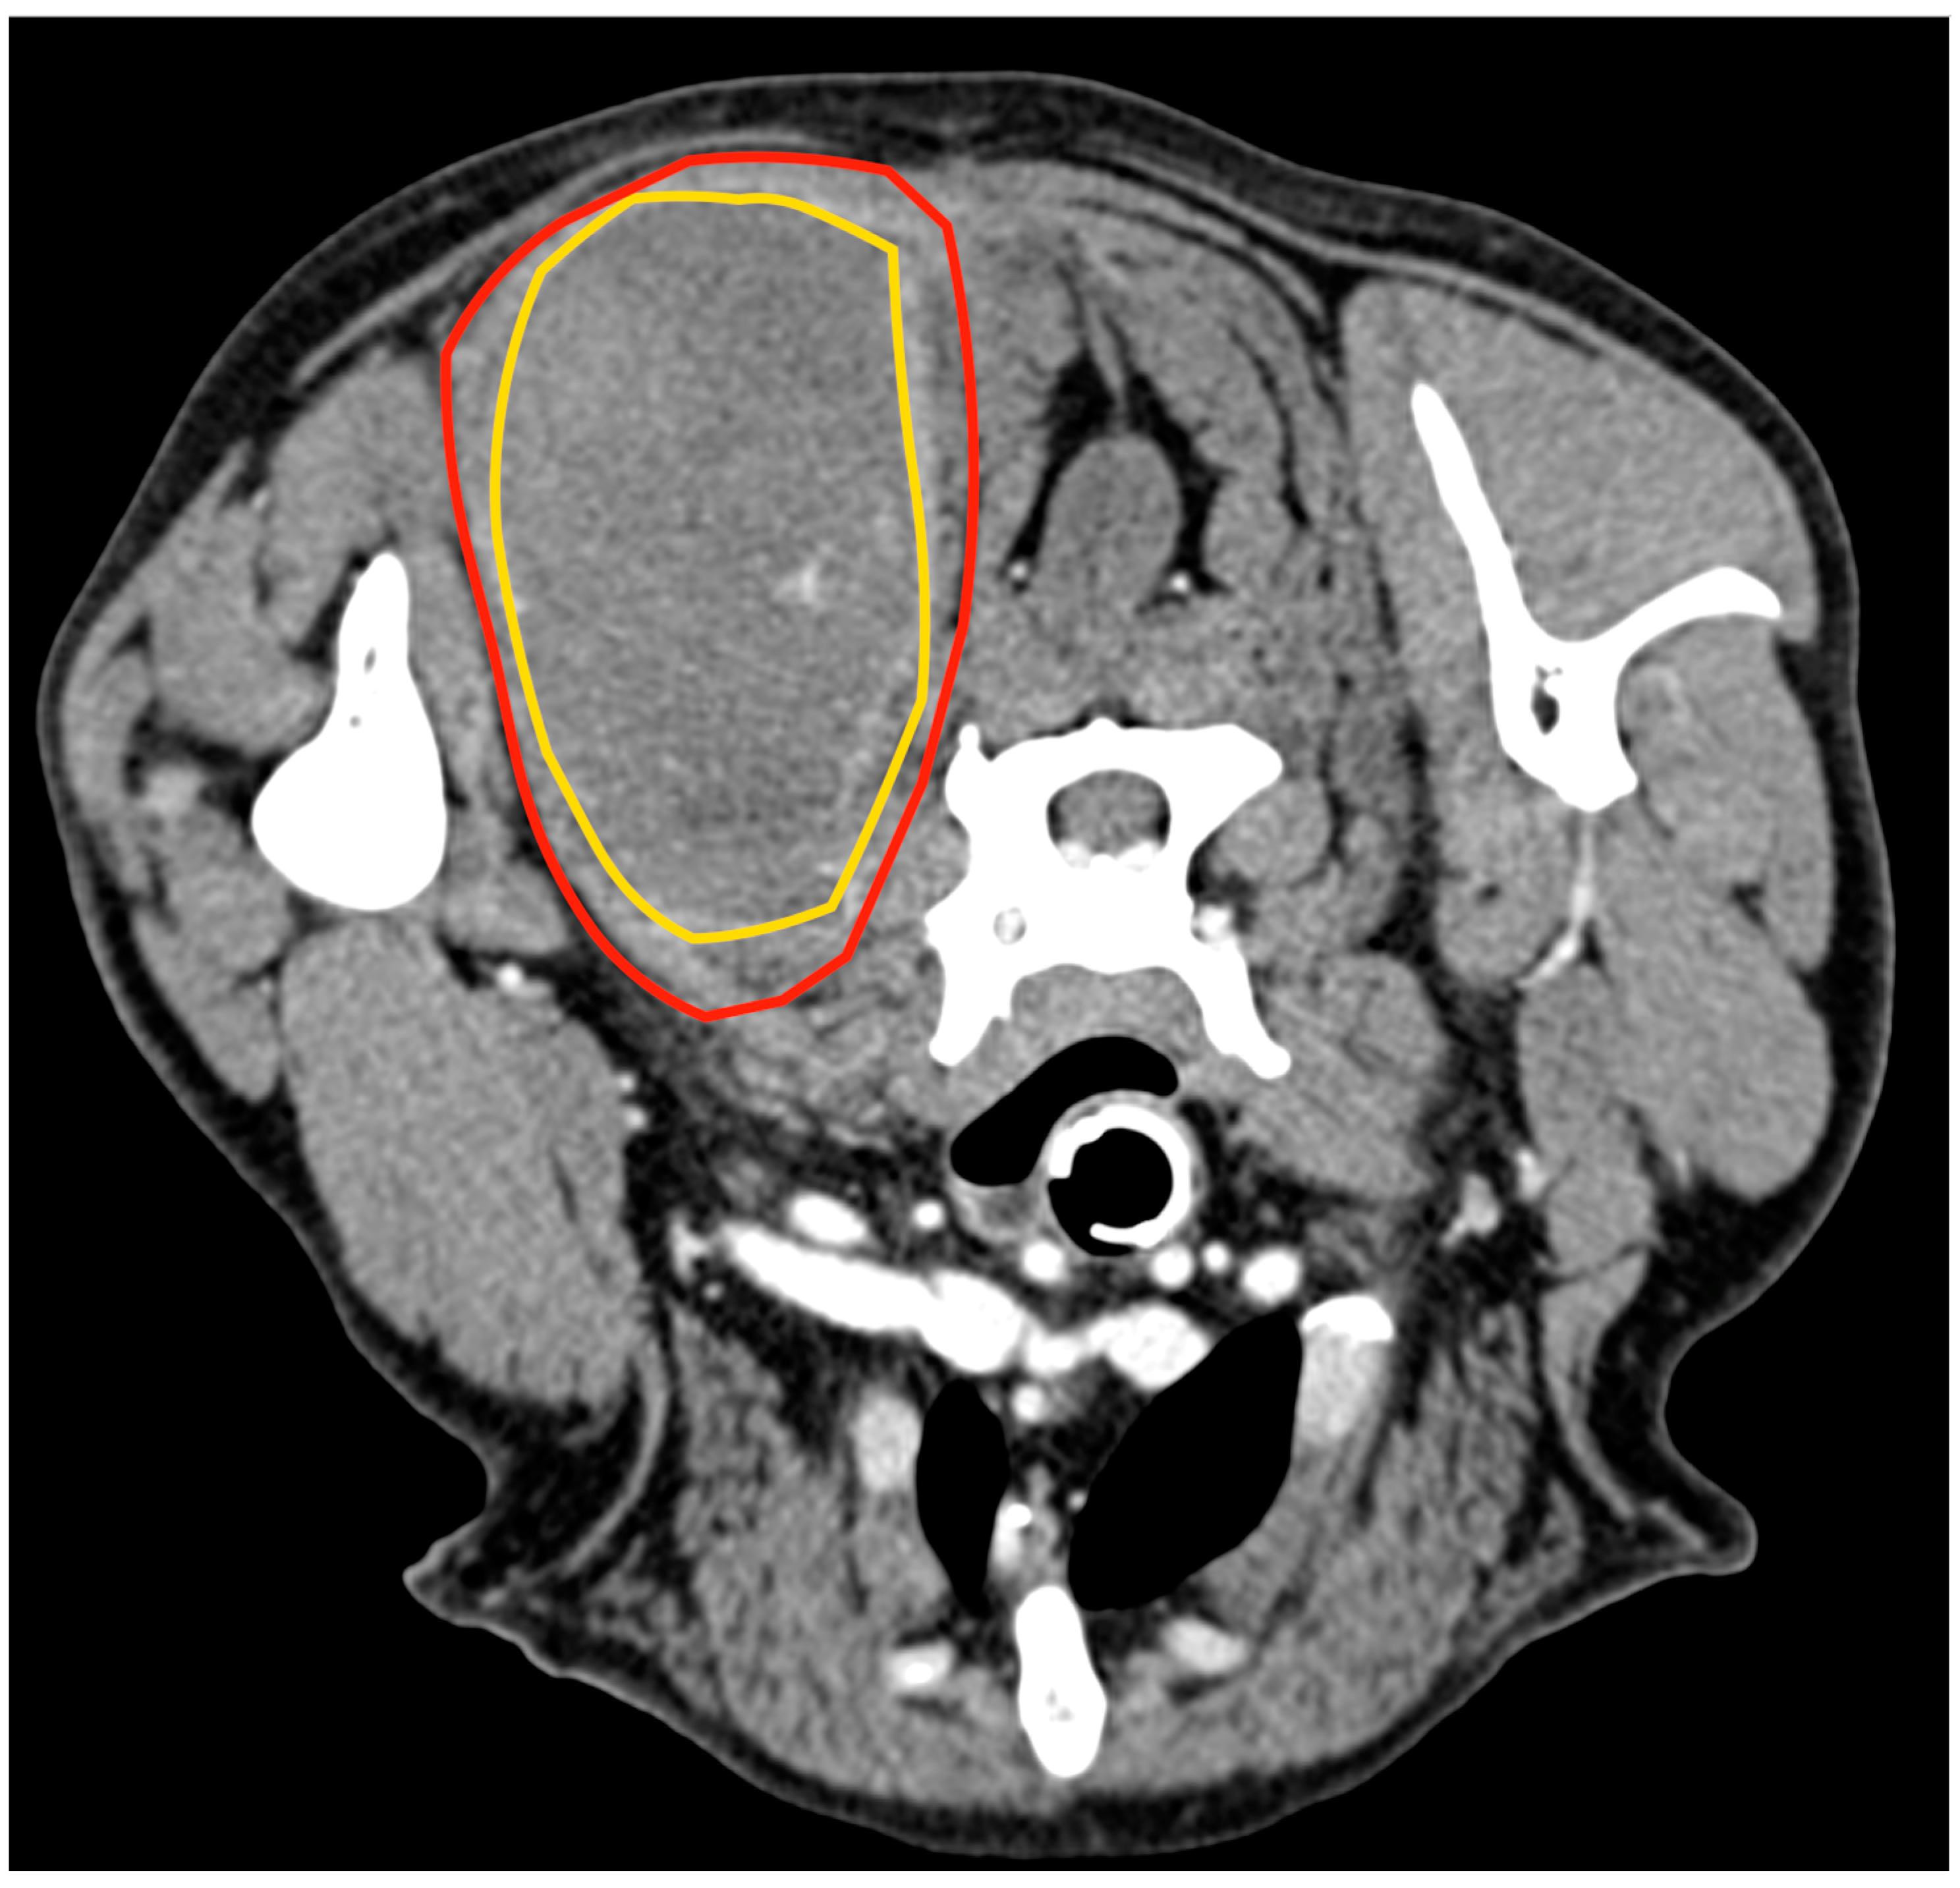

Cytology of the lesion via fine needle aspiration (FNA) was not diagnostic; therefore, an incisional biopsy was performed at the time of the total body CT. This revealed a 5.8 cm × 5.5 cm, poorly defined mass confined within the biceps femoris muscle, with heterogeneous enhancement after the administration of an intravenous contrast medium (Figure 2). No lesions suggestive of metastatic spread were observed. The histology from the bioptic sample was morphologically suggestive of PWT.

Figure 2.

Tomographic appearance of the sarcoma within the biceps femoris muscle, axial view (A). The yellow line delimitates the tumours, the red line the biceps muscle 3D reconstruction, and the white arrow indicates the tumour (B).